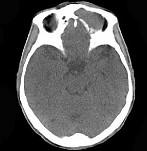

问题 男,53岁,左眼痛,突出3年,请结合影像,选择最可能的诊断 ( )

选项 A、眼型Graves病 B、良性混合瘤 C、骨膜下脓肿 D、黏液囊肿 E、淋巴瘤

答案 D